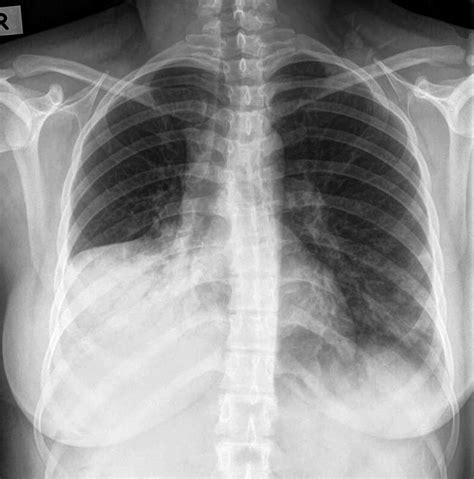

ARDS is a complex syndrome that can be triggered by various factors, including sepsis, pneumonia, trauma, and aspiration. It is marked by the rapid onset of bilateral pulmonary infiltrates, refractory hypoxemia, and decreased lung compliance. The Ards Chest X Ray is instrumental in visualizing these pulmonary infiltrates, which appear as diffuse, bilateral opacities on the radiograph.

The Ards Chest X Ray is often the first imaging modality used to evaluate patients suspected of having ARDS. It provides a quick and relatively inexpensive way to assess the lungs for signs of inflammation and edema. Key findings on an Ards Chest X Ray include:

• Bilateral pulmonary infiltrates

• Diffuse opacities

• Air bronchograms (air-filled bronchi surrounded by consolidated lung tissue)

• Absence of pleural effusions or cardiomegaly

These findings, when combined with clinical criteria such as the PaO2/FiO2 ratio (the ratio of arterial oxygen partial pressure to fractional inspired oxygen), help confirm the diagnosis of ARDS.

• Bilateral Infiltrates: ARDS typically presents with bilateral, diffuse infiltrates that are often more pronounced in the dependent lung zones.

• Air Bronchograms: These are visible air-filled bronchi within consolidated lung tissue and are a hallmark of ARDS.

• Absence of Pleural Effusions: Unlike other causes of pulmonary edema, ARDS is usually not associated with significant pleural effusions.

• Cardiomegaly: The heart size is typically normal in ARDS, helping to differentiate it from cardiogenic pulmonary edema.